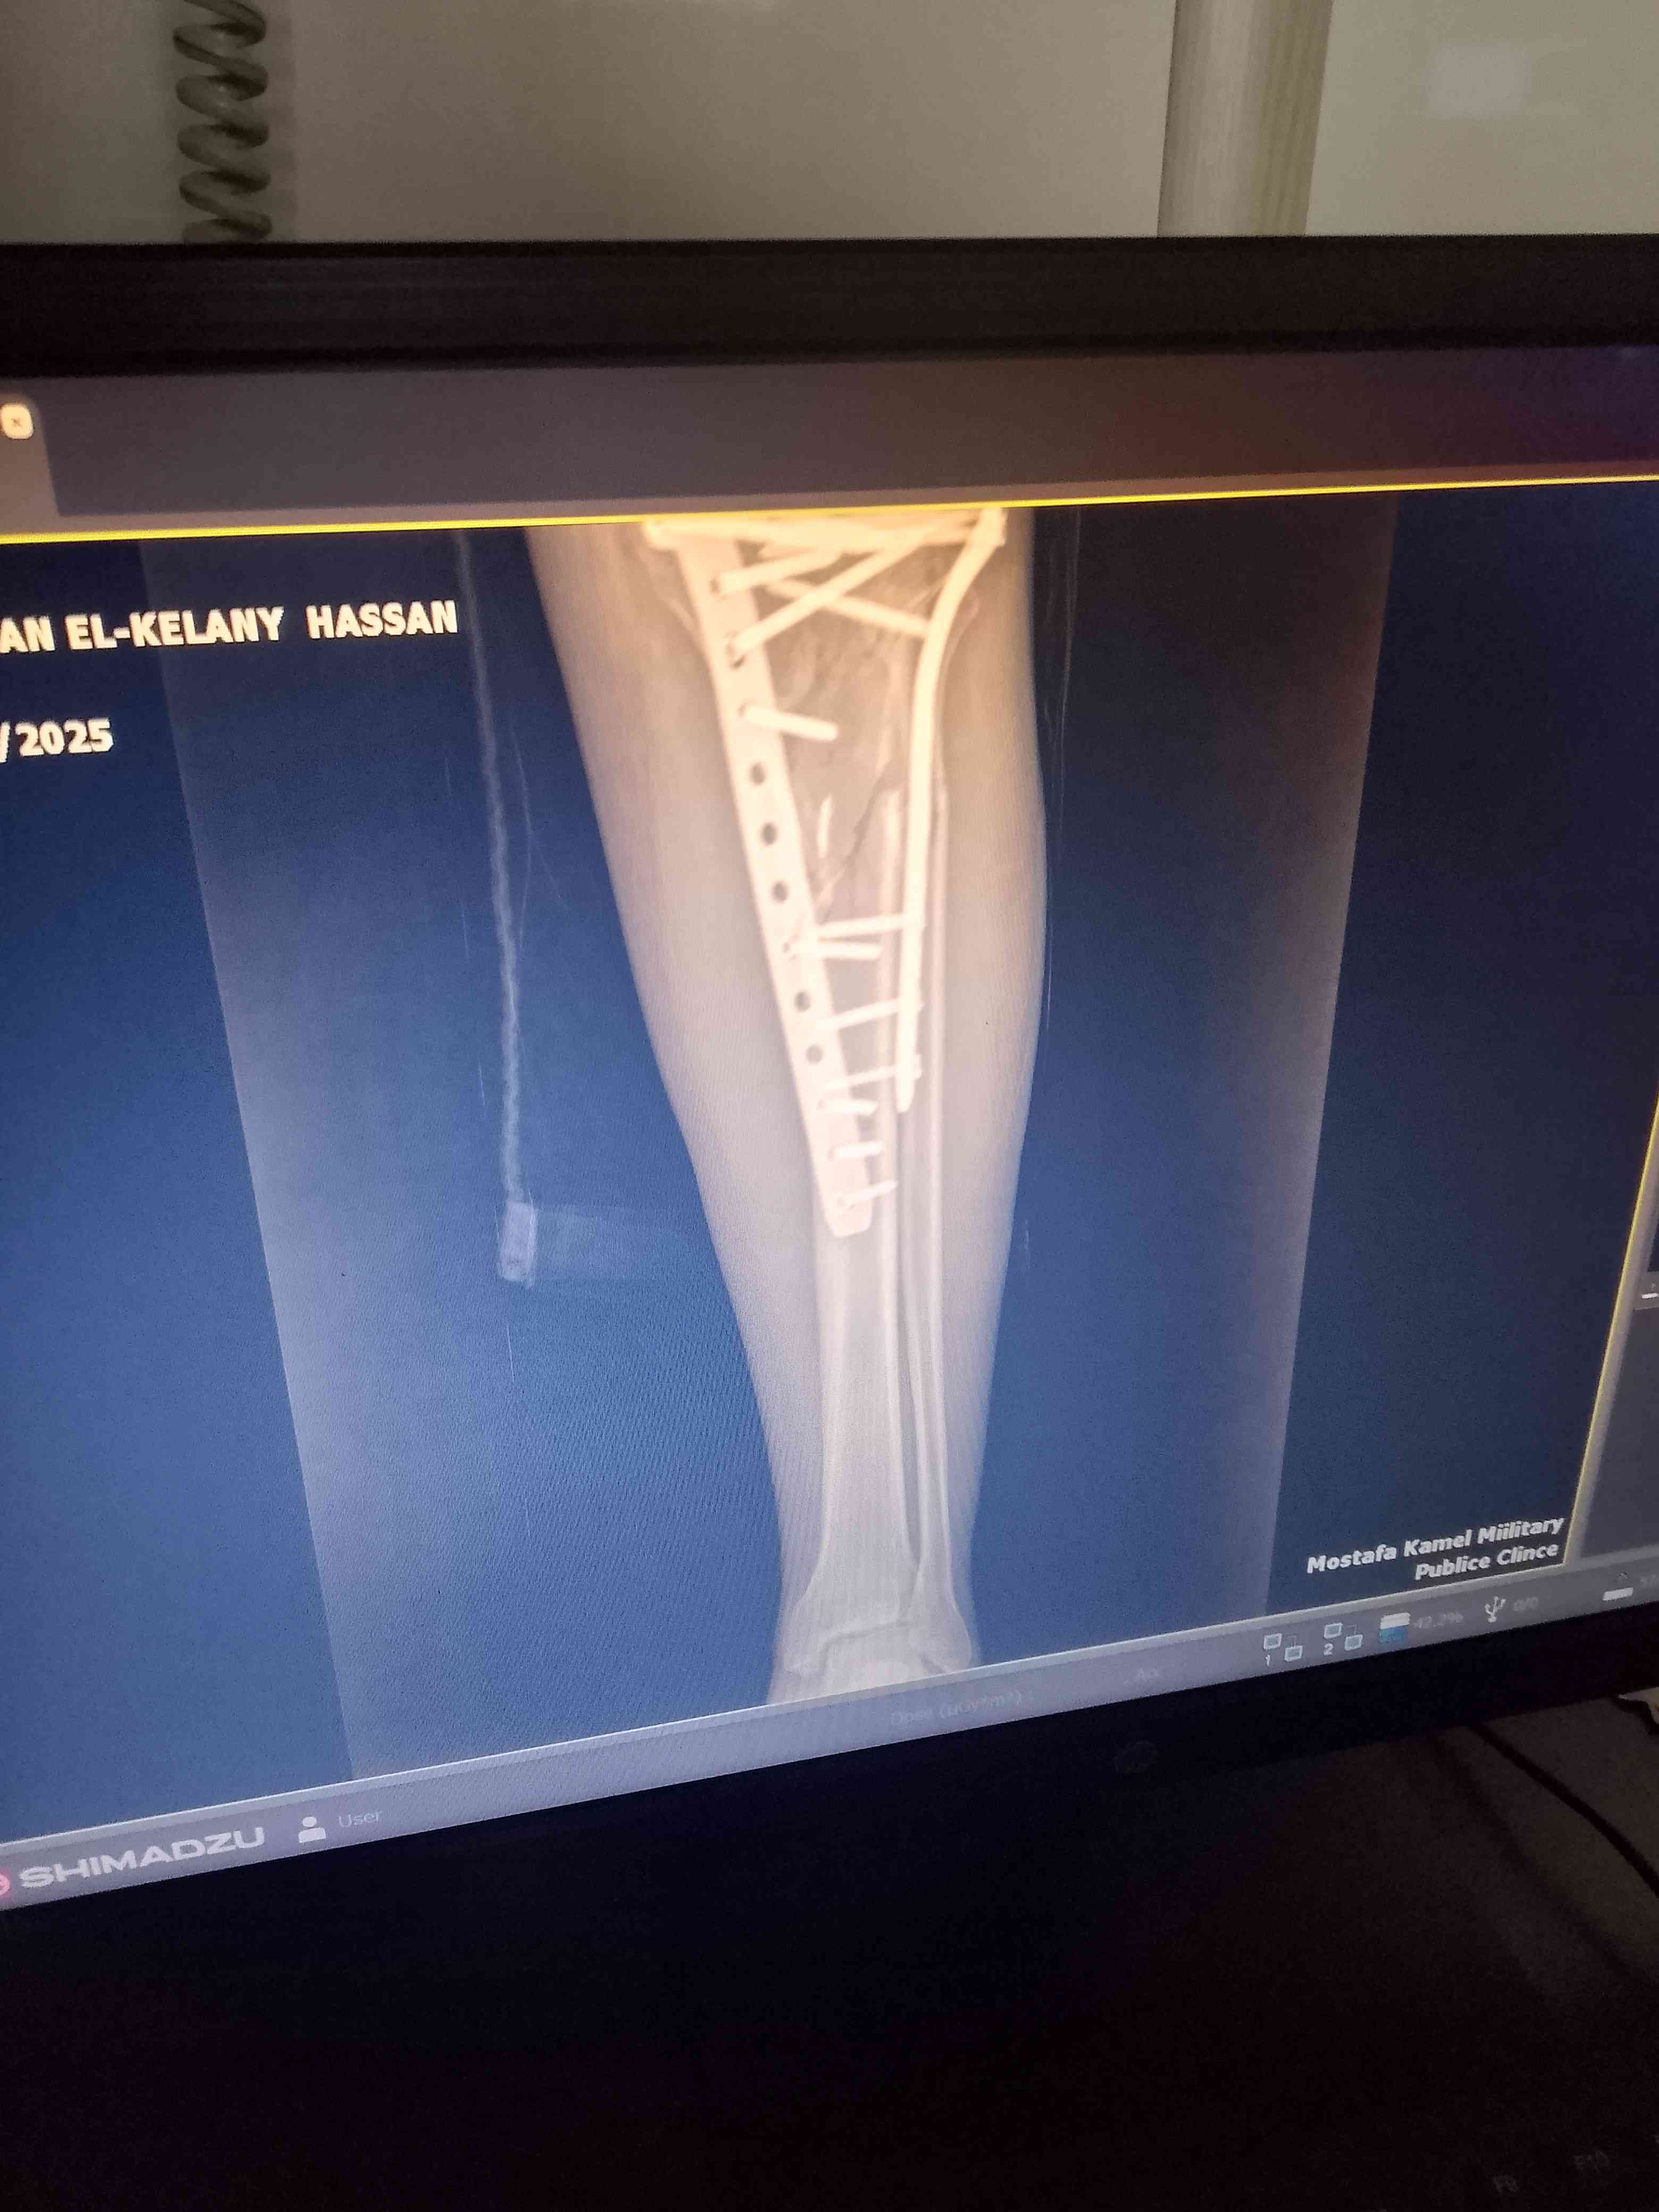

كسر عظام فى ساق الرجل اليسرى